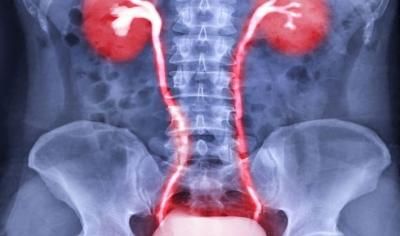

هناك العديد من الأسباب التي تؤدي إلى حرقان البول، من أبرزها: القسطرة البولية، ارتفاع سكر الدم، قلة شرب السوائل، وجود حصوات في المسالك البولية (الكلى، الحالبين، المثانة)، التهيج الكيميائي الناتج عن استخدام مواد التنظيف (الصابونة أو الشامبو)، الانسداد الكلي أو الجزئي في الحالب، متلازمة المثانة المؤلمة، التهابات المسالك البولية، والأمراض المنقولة جنسياً.